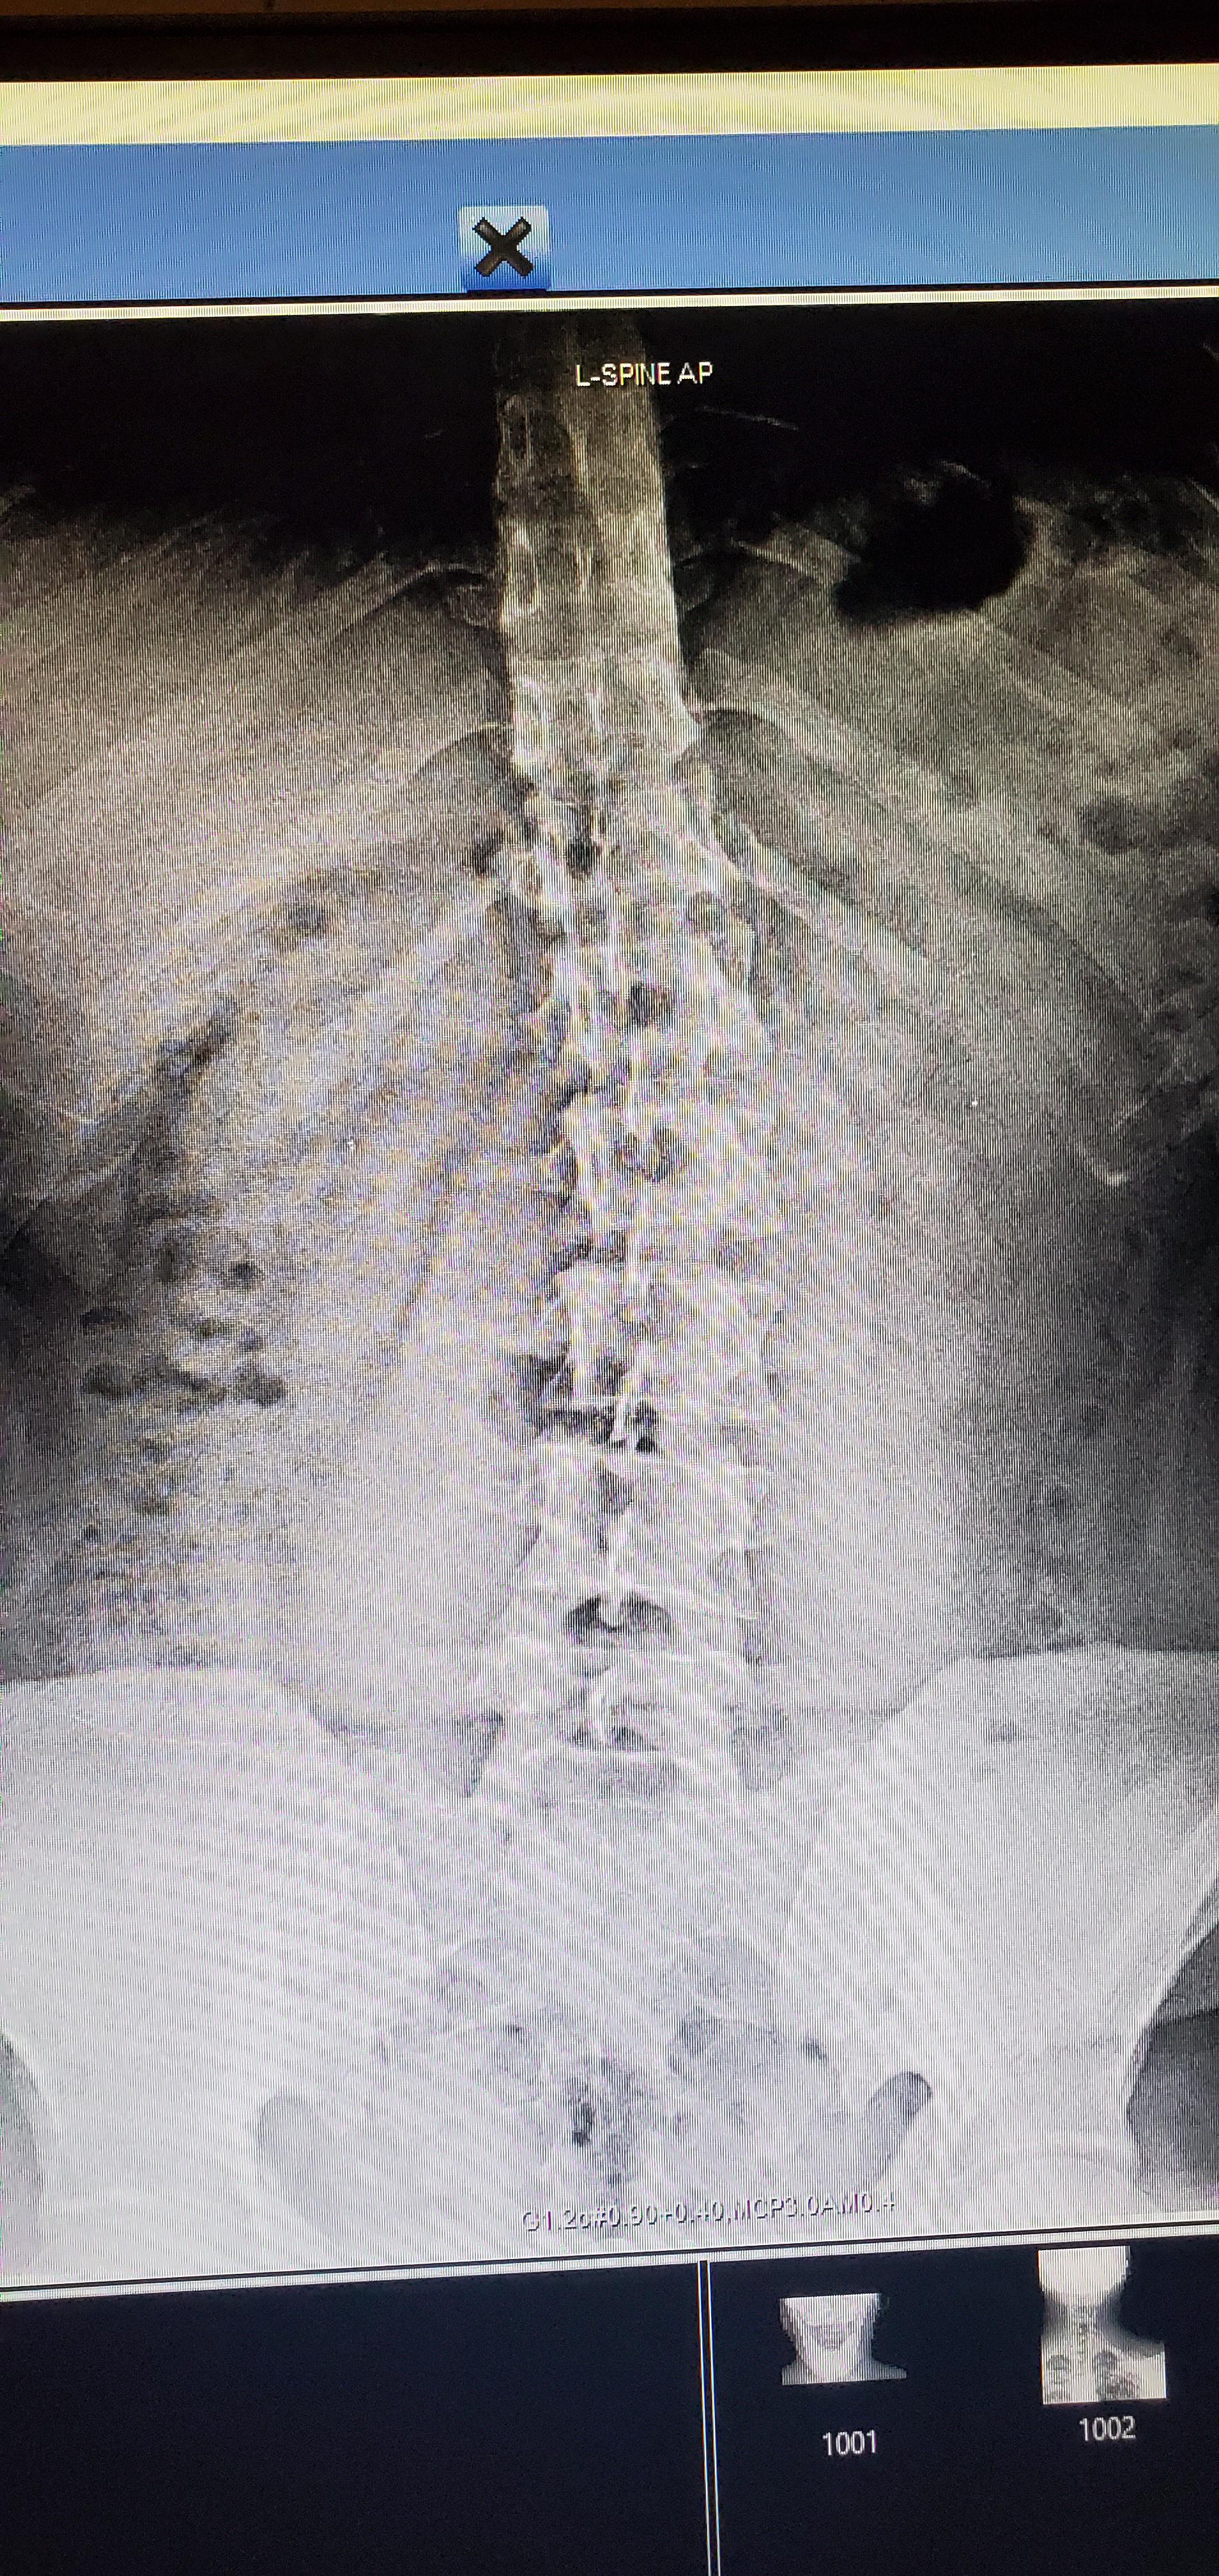

Scoliosis Caused By Car Accident . If you have suffered a serious spinal column injury due to a car accident and are suffering from scoliosis, read on and find out. Additionally, car accidents can cause other spine conditions like herniated discs, whiplash, and spinal stenosis, which can. The sudden impact and force exerted on your body during a collision. In some cases, these injuries may. Many people are born with the condition, although the cause is not known. For people who already experience scoliosis symptoms, getting into a car accident can. Car accidents can lead to spinal injuries, potentially affecting the spine’s alignment. Yes, a significant acceleration or deceleration force from an automobile crash can cause the spine to be out of alignment and. Car accidents are one of the leading causes of spinal injuries.

For people who already experience scoliosis symptoms, getting into a car accident can. If you have suffered a serious spinal column injury due to a car accident and are suffering from scoliosis, read on and find out. Many people are born with the condition, although the cause is not known. The sudden impact and force exerted on your body during a collision. Car accidents are one of the leading causes of spinal injuries. Additionally, car accidents can cause other spine conditions like herniated discs, whiplash, and spinal stenosis, which can. Car accidents can lead to spinal injuries, potentially affecting the spine’s alignment. In some cases, these injuries may. Yes, a significant acceleration or deceleration force from an automobile crash can cause the spine to be out of alignment and.

Scoliosis Caused By Car Accident For people who already experience scoliosis symptoms, getting into a car accident can. In some cases, these injuries may. If you have suffered a serious spinal column injury due to a car accident and are suffering from scoliosis, read on and find out. Car accidents can lead to spinal injuries, potentially affecting the spine’s alignment. Yes, a significant acceleration or deceleration force from an automobile crash can cause the spine to be out of alignment and. Many people are born with the condition, although the cause is not known. For people who already experience scoliosis symptoms, getting into a car accident can. The sudden impact and force exerted on your body during a collision. Car accidents are one of the leading causes of spinal injuries. Additionally, car accidents can cause other spine conditions like herniated discs, whiplash, and spinal stenosis, which can.